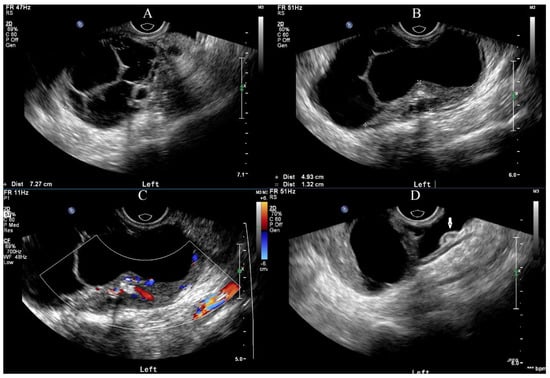

A right ovarian immature teratoma, grade 2, stage IC2 was diagnosed based on the FIGO stage classification for ovarian tumors. A chemotherapy regimen including bleomycin, etoposide, and cisplatin (BEP) was given for three cycles based on the NCCN clinical guidelines for ovarian germ cell tumors. AFP levels quickly decreased from 27.8 ng/mL to normal after two cycles of chemotherapy, and the last cycle was completed in mid-March 2022. The serum CA19-9 was less than 2 U/mL before surgery. Repeat ultrasonography conducted one month after the surgery did not show any abnormalities, but an ultrasound examination on five days after the last cycle of chemotherapy showed an approximately 8-cm solid cystic mass located in the left posterior uterus. The patient was then referred to our hospital. A repeat blood draw showed that serum AFP, CA125, NSE, and CA19-9 were all within normal ranges. Recurrence of immature teratoma and progressive disease could not be excluded. Further ultrasonography conducted by an expert demonstrated an 8.0 × 7.3 cm mixed-echo, lobulated mass with clear boundaries in the left adnexal area. The presence of lipid and hair-like echo, as well as a CDFI that revealed only scattered, short strips of blood flow signals in a small portion of the mass, were suggestive of GTS (Figure 2). Enhanced abdominal-pelvic CT was also used to determine the diagnosis and showed a comparable result to the ultrasound (i.e., a solid 8-cm cystic mass with undetermined malignancy), and no enlarged retroperitoneal lymph node was observed (Figure 3).

Figure 2. Ultrasonic features of the mass. (A) A multilocular solid-cystic mass with a clear boundary was seen in the left adnexal area, in which lipid and hair-like hyper-echo mass was also observed. (B) Calcification can be seen in solid hypo-echo of the mass. (C) The CDFI revealed scattered, short strips of blood flow signals in the solid proportion of this mass. (D) Implant nodules can be seen on the intestinal surface.